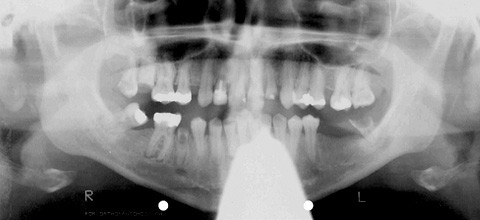

In der vorliegenden Kasuistik wird die oralchirurgische Behandlung einer durch einen Hirntumor körperlich und geistig behinderten Patientin geschildert, die anstatt einer ursprünglich empfohlenen Behandlung in Narkose eine Therapie unter kombinierter Lokalanästhesie/Hypnose wünschte. Trotz erheblicher ärztlicher Bedenken erwies sich die Patientin als ausgezeichnet trancefähig und erlebte die Behandlungssitzungen nahezu stressfrei. Eine ausgedehnte chirurgische Zahnsanierung konnte